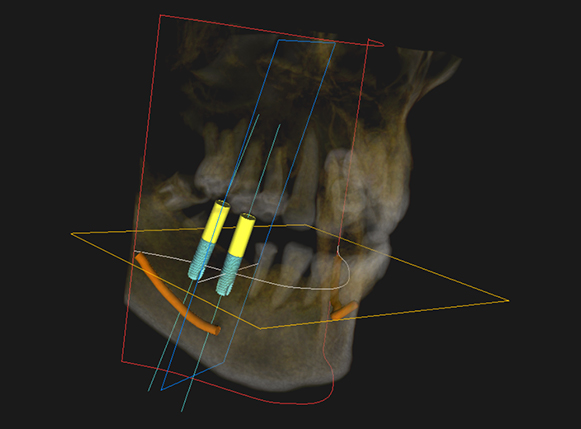

術前のCTでのシュミレーション

インプラント手術を安全に行うためには「従来の2次元のレントゲン」 だけではなく、「三次元レントゲン(歯科用CT)」が必須です。

当院ではインプラント治療に関しては必ずCT撮影を行い、事前に診査・診断を行います。(インプラント相談と治療の際のCT撮影は無料。通常12,000円(税別))

オレンジ色で示した部分が「下顎管」といって、顎の大事な「神経と血管」 が走行しています。これを傷つけてしまうと麻痺などの偶発症を引き起こすことがあります。

当院では適切な位置にインプラントを埋入するためにCT撮影とステント(埋入方向を定める装置) を使用し、より安全に手術を行うことに努めておりますので安心して治療を受けて頂くことが可能です。

術後に適切な位置に埋入完了

術後のCT画像からも、シミレーション通り適切な位置にインプラントを埋入出来ていることが確認できます。